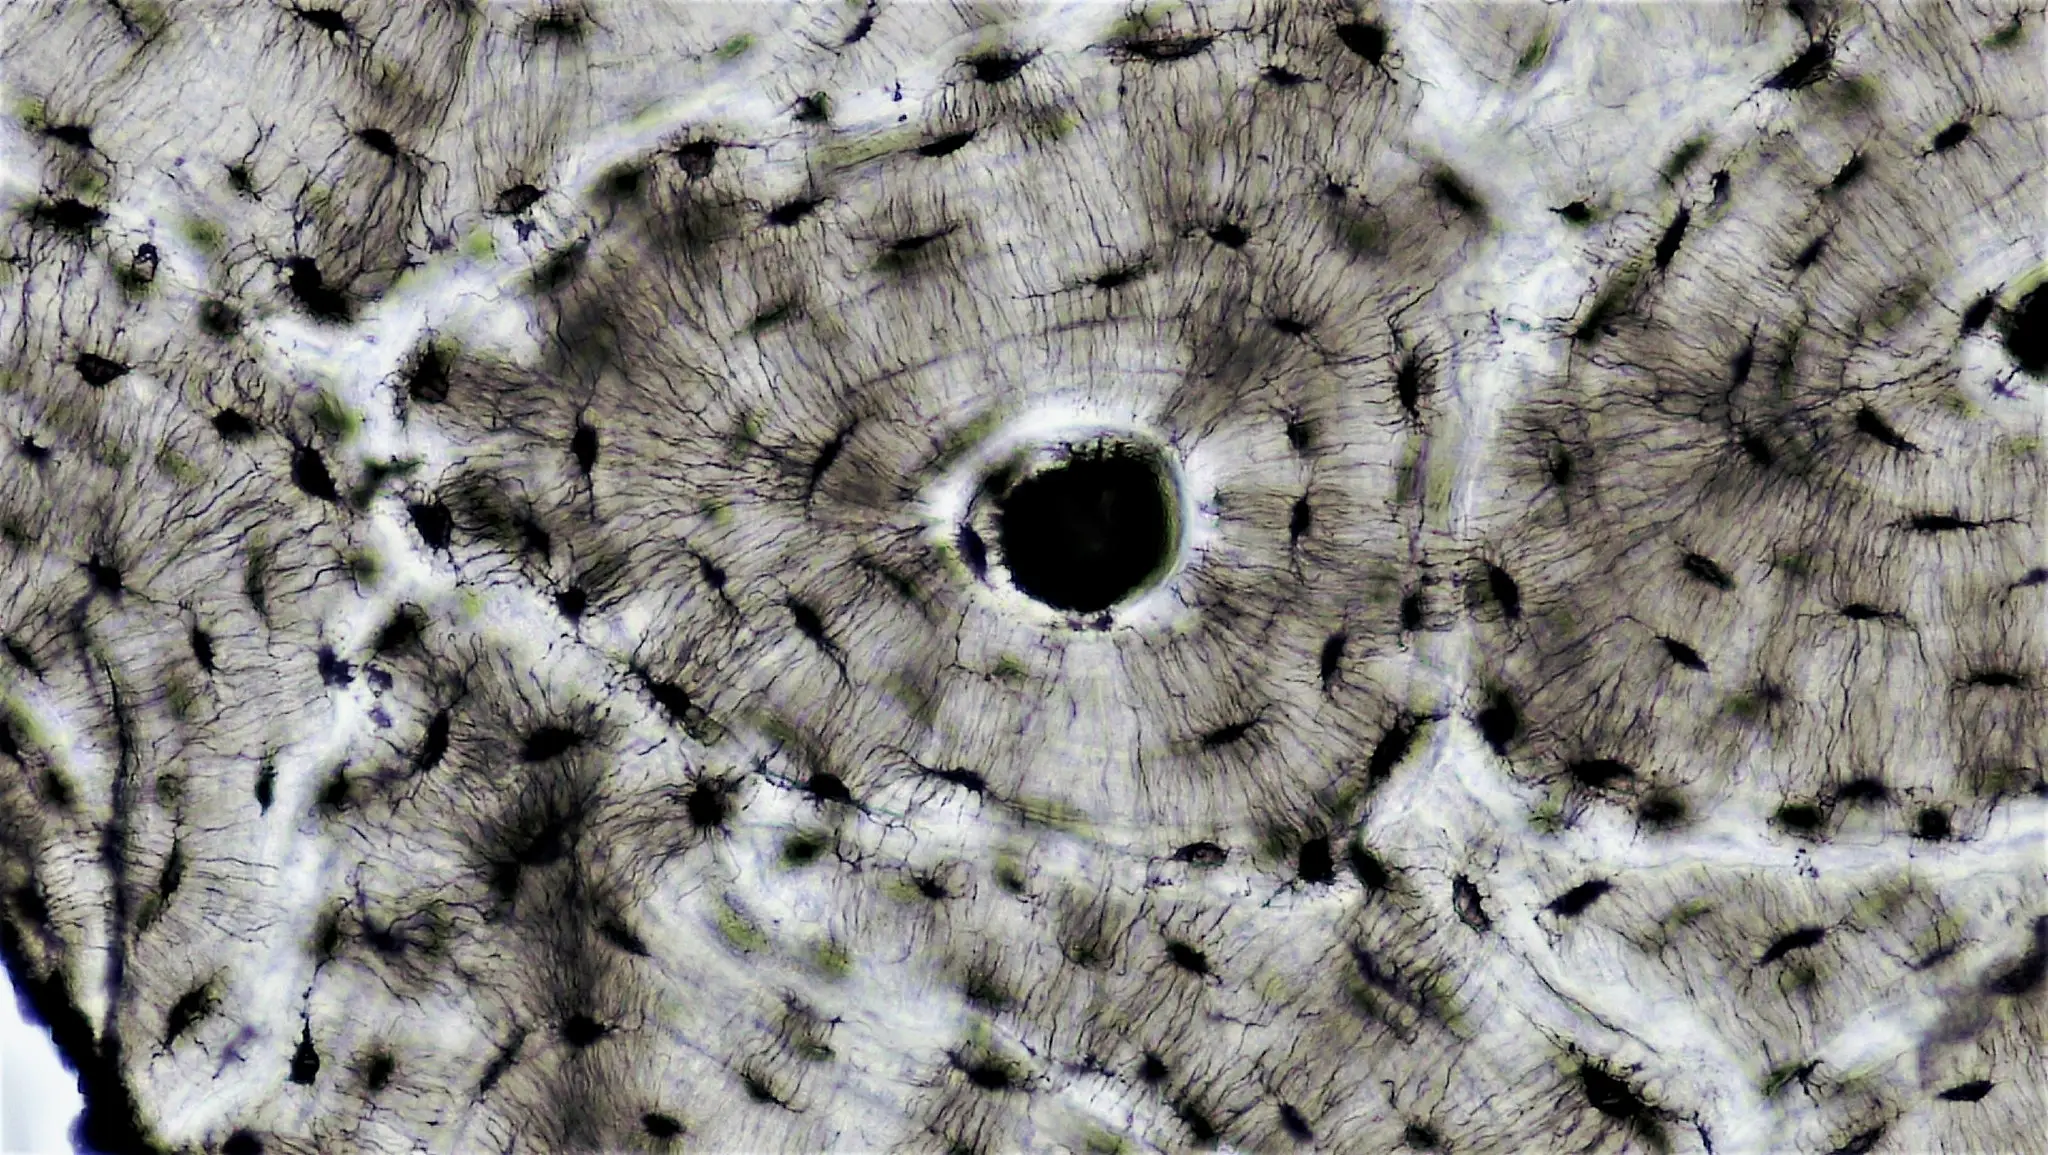

La comprensione del connettoma osteocitario aiuta a capire come le cellule ossee comunicano durante il rimodellamento che avviene durante la guarigione.

Diagramma che illustra il microambiente del midollo osseo e i meccanismi cellulari coinvolti nell

Tratto da https://link.springer.com/article/10.1186/s13287-025-04288-4 C.C. 4.0